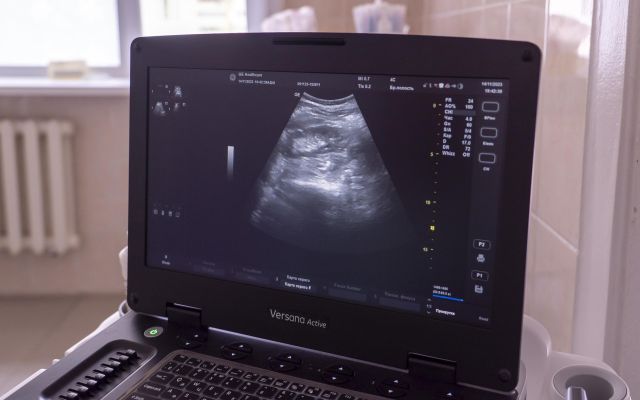

Новый аппарат УЗИ и цифровой флюорограф теперь есть в распоряжении отделения лучевой диагностики горбольницы им. С.П. Боткина в Орле. Оборудование закуплено в рамках нацпроекта «Здравоохранение» и программы «Модернизация первичного звена здравоохранения», сообщили в депздраве Орловской области.

Новый аппарат УЗИ РуСкан60, как отметили в ведомстве, информативнее предшественников. Используемая в нем современная технология цифрового луча дает изображение высокого качества. Подходит для обследования брюшной полости, сердца, сосудов, костно-мышечной системы.